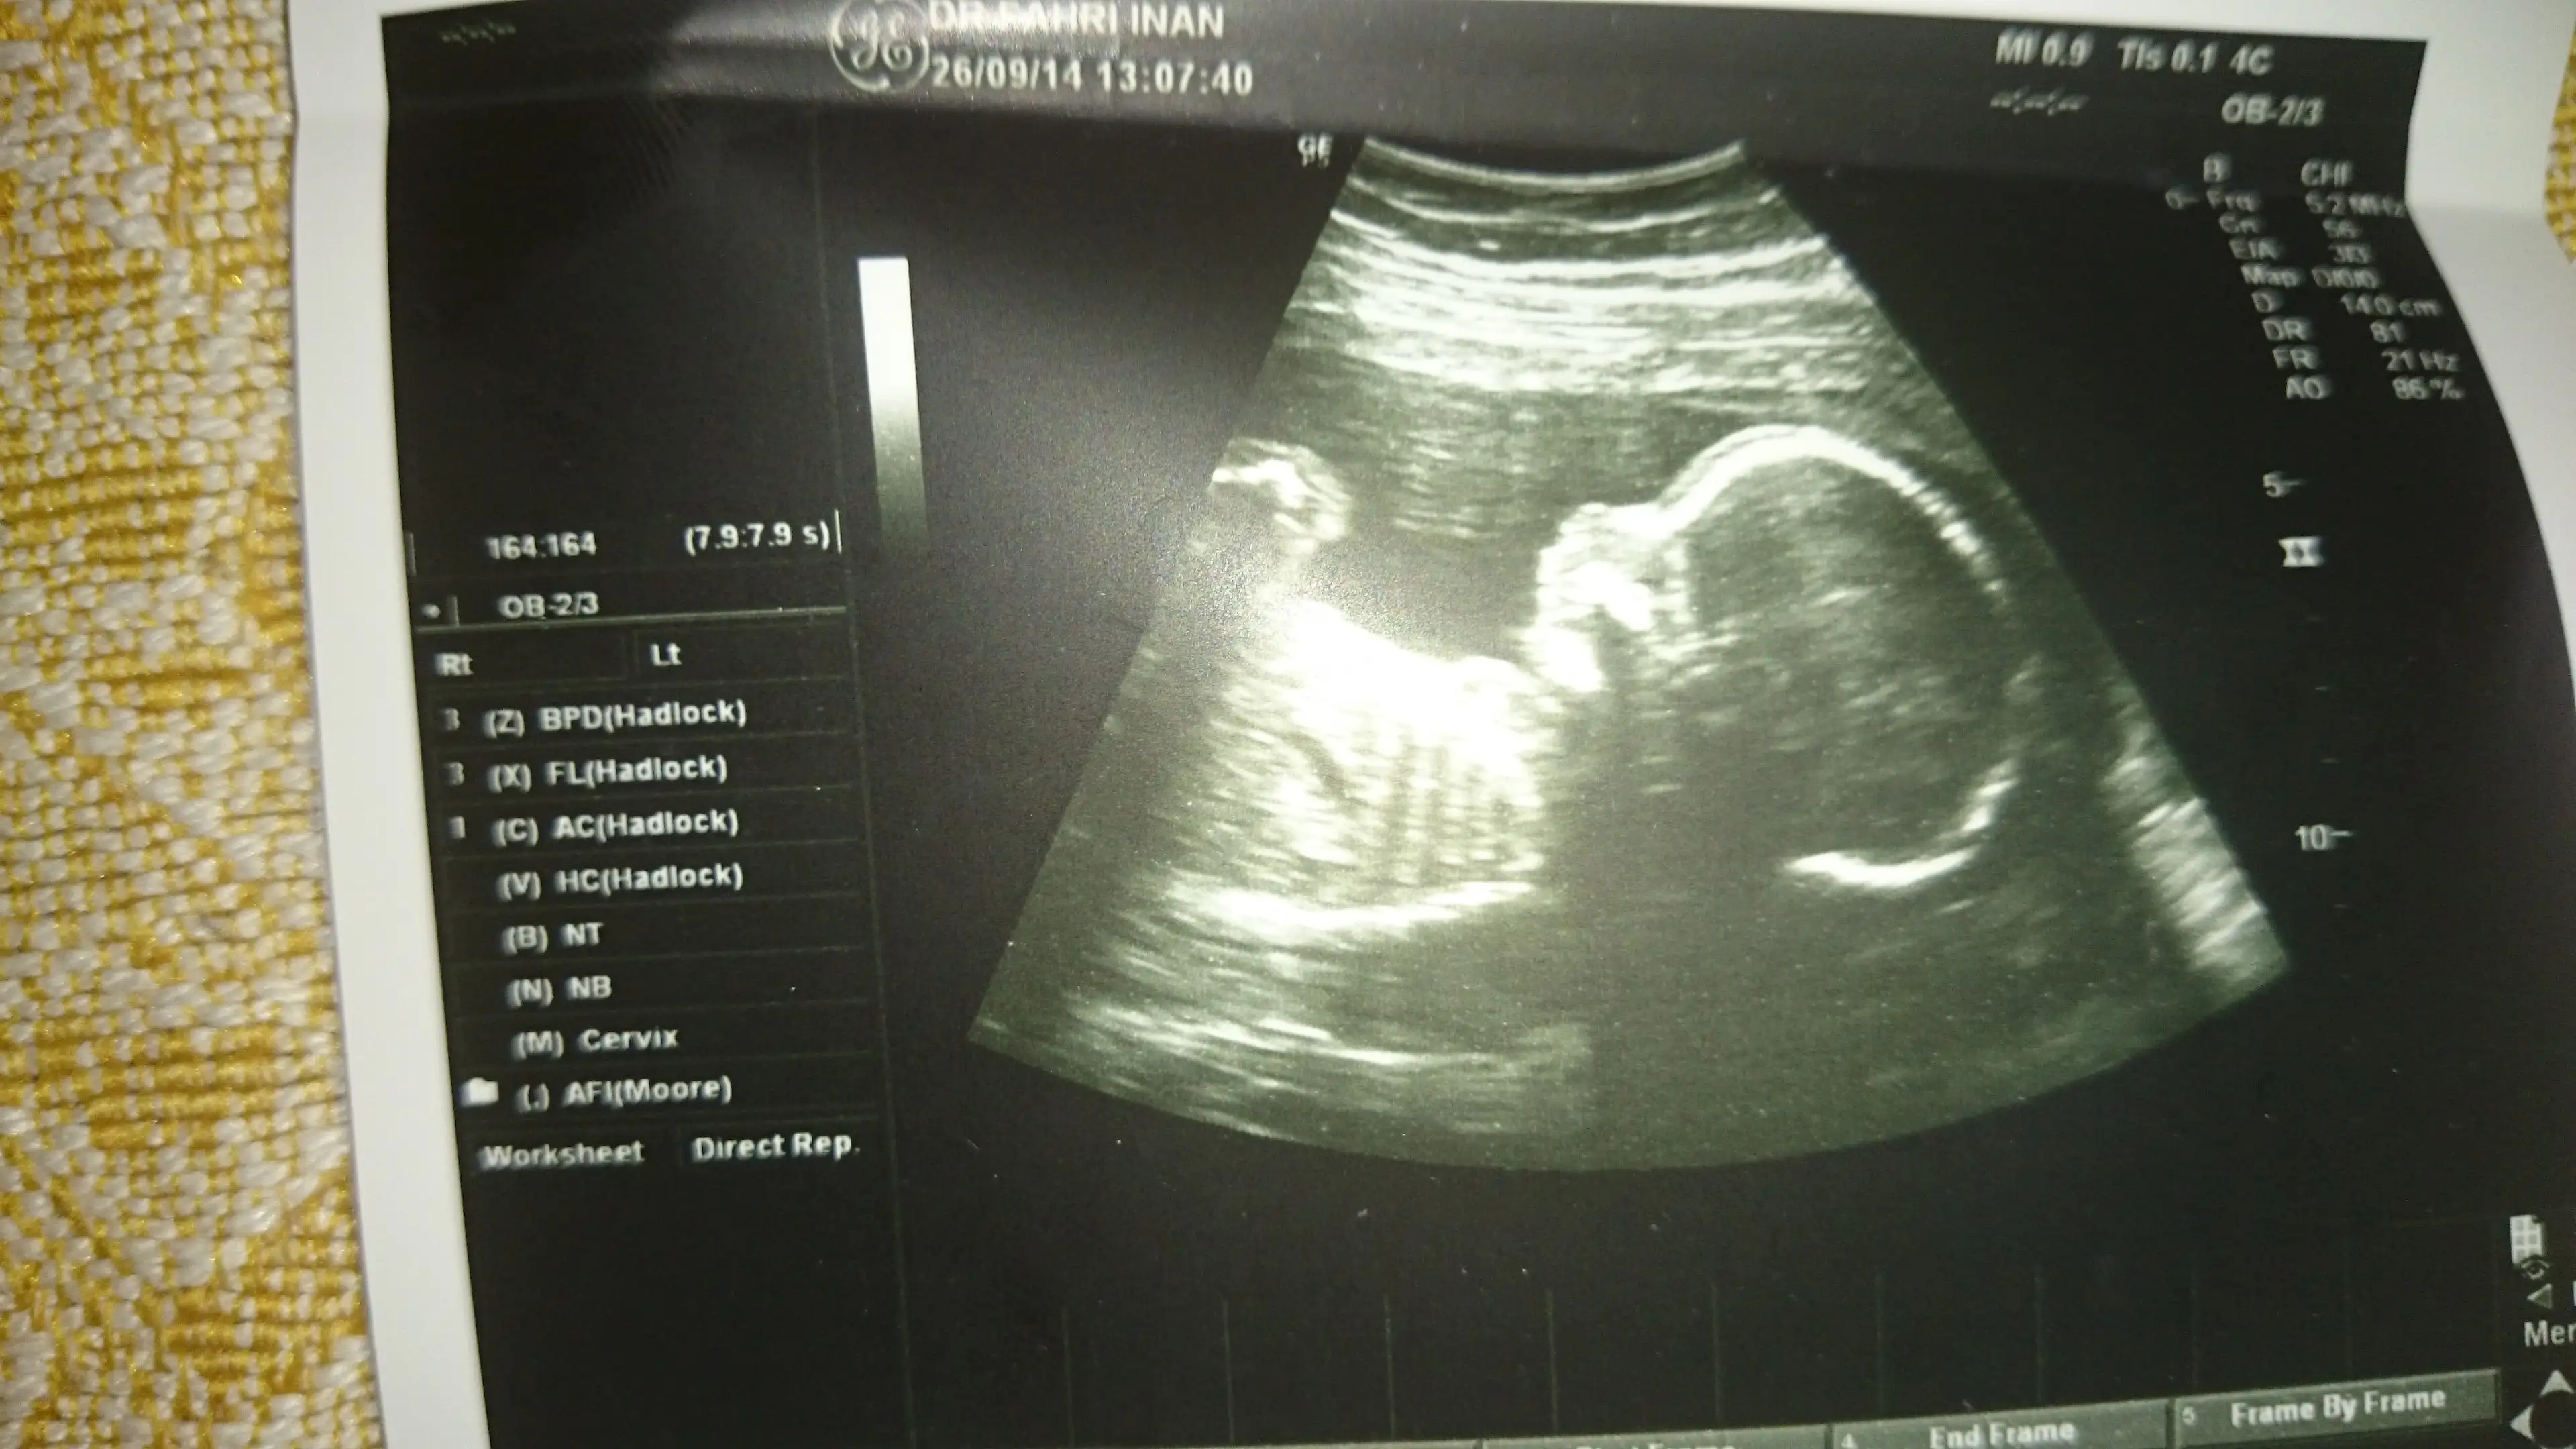

bugun detaylıya gırdık oglusla kızlar.. plesenta prevıa durumu vardı bende..ılk doğumum normal dı sımdı sezeryan olmak dusuncesı benı ınanılmaz korkutuyordu(cok korkuyorum cunku)

netıce ıtıbarıyle bu durumun ortadan kalktığını ve plesantanın normal yerıne gectıgını ogrendık bugun.. ınanamadım defalarca kez sordum dr a emınmısınız dıye..cok mutlu olduk esımle..hamdolsun hep hayırlısını ıstemıstım ..sukurler olsun bınlerce kez.. oglus 21+4 günlük 434 gr olmuş..